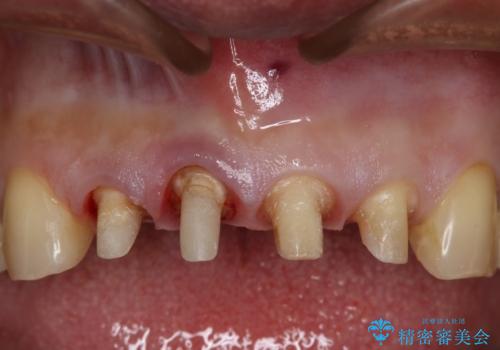

神経を取っている右上2番目の歯は根尖部に病巣があったため根管治療をした上で土台を立て、被せ物の作製を行いました。右上1番目の歯は他院にてとても大きく深い金属の土台が入れられており被せ物の色調に影響を与えていましたが、すべて取りきることのリスクが高いため途中まで除去し目立ちにくいファイバーコアで補強と色調の改善を行いました。